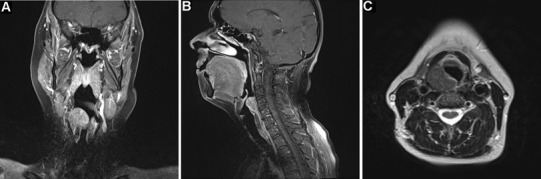

An MRI neck with contrast delineated a 28 mm diameter mass centred on the right piriform fossa and extending into the right supraglottis without associated lymphadenopathy (Fig. 1). Clinical and radiological features were suggestive of a benign nature and, consequently, transoral laser microsurgery was planned.

Fig. 1.

MRI scans with contrast demonstrating an enhancing mass centered on the right piriform fossa a T1-weighted coronal, b T1-weighted sagittal, c T2-weighted axial